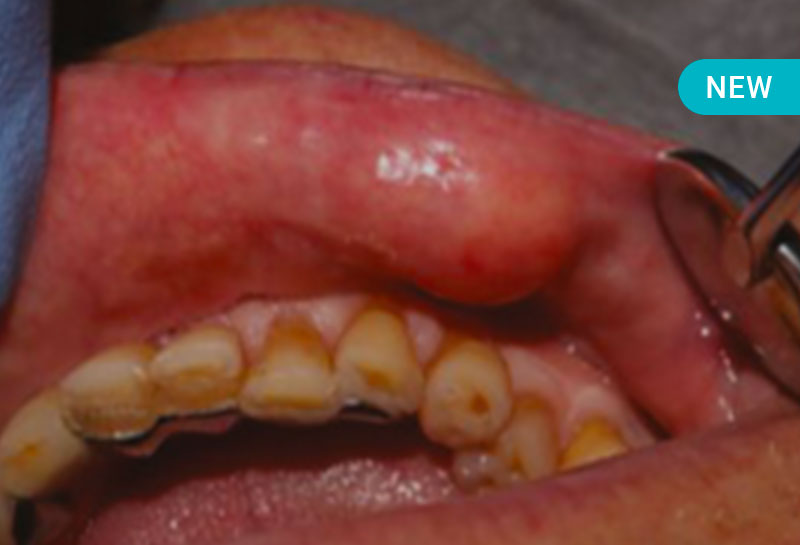

Des lésions élémentaires (macules, plages, plaques, papules, ulcérations, érosions, vésicules, bulles, nodules) aux pathologies orales les plus graves comme les toxidermies et les cancers en passant par les infections sexuellement transmissibles (IST), il est important pour chaque chirurgien-dentiste de savoir repérer une lésion dermatologique buccale pour la diagnostiquer et ne plus passer à côté.

Au travers de nombreux cas cliniques, cette formation va vous permettre d’acquérir les compétences nécessaires pour accompagner vos patients dans toutes les situations de lésions buccales mais aussi connaître leurs facteurs de risque afin de pouvoir mieux accompagner vos patients grâce à leur prévention.

- Dépistage d’une lésion précancéreuse